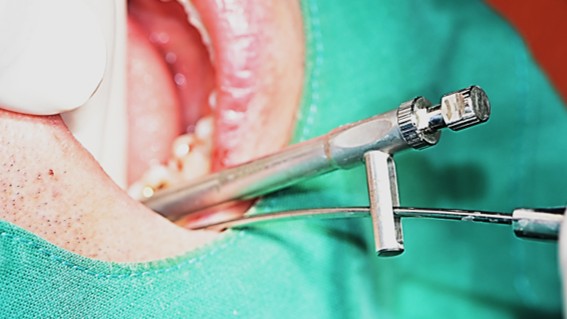

Single implant (staged) Arum NB1, f/u